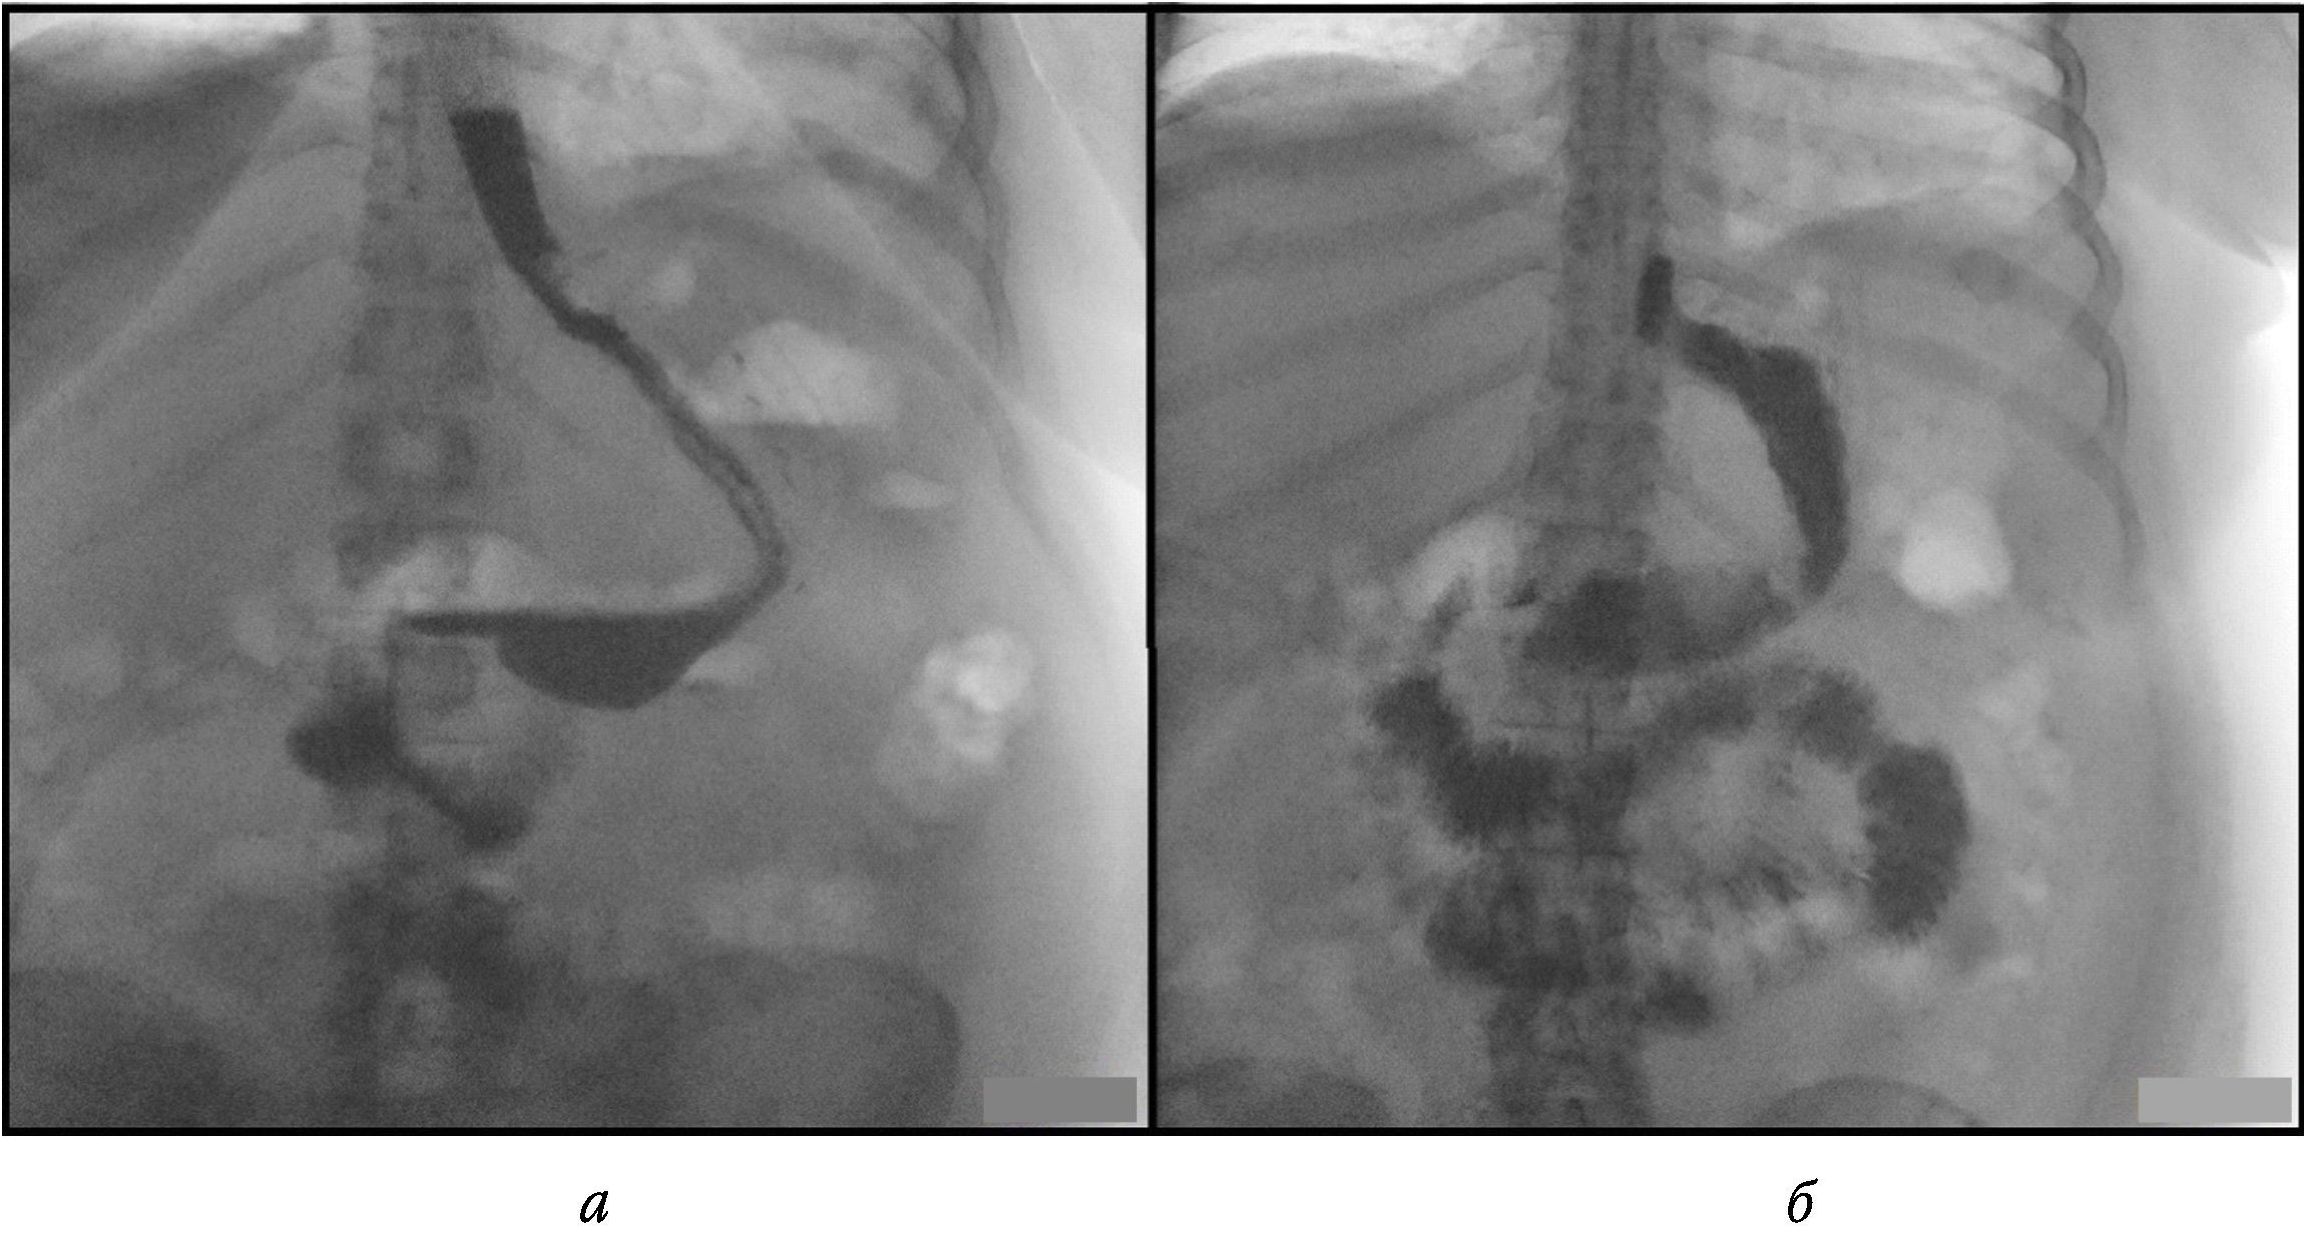

05.05.2023 пациентке была выполнена релапароскопия. В брюшной полости имелся мутный серозный выпот, петли кишок физиологической окраски, без налета фибрина. Место несостоятельности скрепочного шва желудка визуализировать не удалось, обнаружен и вскрыт абсцесс объемом около 50 мл в области предполагаемой несостоятельности, в полость которого установлен трубчатый дренаж. Также были установлены дренажи в малый таз и надпеченочное пространство. Назначена антибактериальная терапия препаратами резерва: меронем (1 г 3 раза в сутки) и ванкомицин (1 г 2 раза в сутки) внутривенно. В течение первых суток после релапароскопии пациентка была активизирована, проводилось парентеральное питание. Сброс по дренажу из полости абсцесса на вторые сутки прекратился, гипертермии и пареза кишечника не было, но сохранялся лейкоцитоз до 16,5 · 109/л, повышение СРБ до 192 мг/л и прокальцитонина до 1,8 нг/мл (референсные значения: до 0,5). Выполнена питьевая проба с водой, а также рентгеноскопия желудка и КТ брюшной полости. При рентгеноскопии пассаж контраста по пищеводу и желудку был сохранен, затеков не обнаружено (рис. 3).

Рис. 3. Контрольная рентгеноскопия желудка с водорастворимым контрастом в прямой проекции, в положении стоя (а) и лежа (б). Данных о сбросе контраста не получено

Однако при КТ (после рентгенологического исследования) в положении пациентки лежа на спине сохранялась ранее выявленная полость абсцесса без тенденции к уменьшению размеров (рис. 4).

Рис. 4. Контрольная мультиспиральная компьютерная томография брюшной полости с пероральным контрастированием. Аксиальная плоскость. Сохраняется заброс контраста по ранее визуализируемому свищевому ходу (красная стрелка) вблизи установленного дренажа (зеленая стрелка), с контрастированием просвета полости (синяя стрелка)